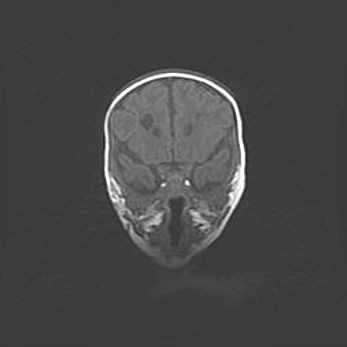

Мальформация Денди-Уокера. Киста задней черепной ямки.

Агенезия мозолистого тела.

Возраст: 2,5 месяца

Вес: 2420 г

Пол: женский

Окружность головы: 37 см

Срок гестации: 32 недели

Мальформация Денди—Уокера — редкий вид патологии ЦНС, представляющий собой врожденный порок развития каудального отдела ствола и червя мозжечка, ведущий к неполному раскрытию срединной (Мажанди) и латеральных (Лушка) апертур IV желудочка мозга. Для этогно синдрома характерна триада симптомов: гипотрофия червя мозжечка и/или полушарий мозжечка, кисты задней черепной ямки, гидроцефалия различной степени. В 70% случаев порок сочетается и с другими аномалиями головного мозга, в частности с агенезией мозолистого тела.